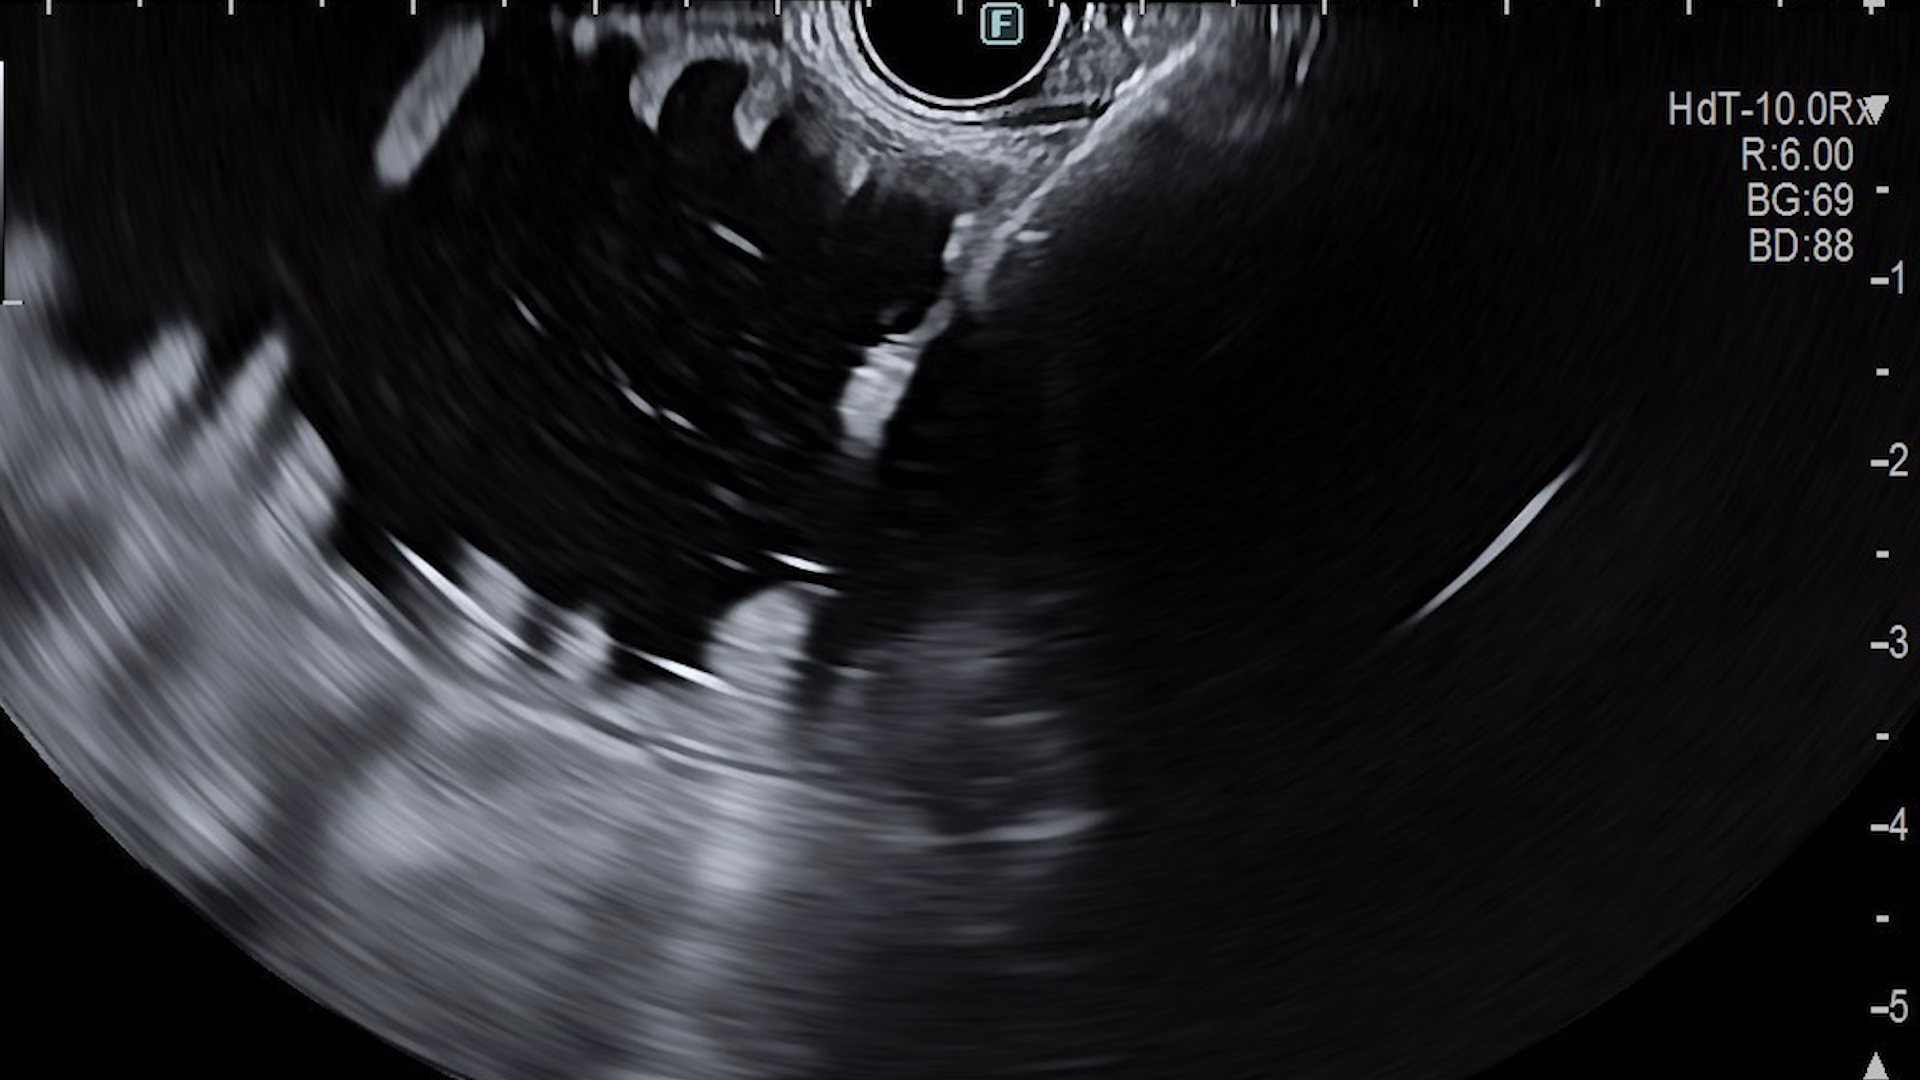

Ținând cont de vârsta pacientului, comorbidități și de refuzul intervenției chirurgicale, s-a decis efectuarea unei gastrojejunoanastomoze ghidate ecoendoscopic, cu stent expandabil metalic de apoziție (de tip LAMS), procedura fiind efectuată în condiții de protezare respiratorie (anestezie generală cu intubație oro-traheală). S-a utilizat tehnica cu sondă nazoenterală, cu instilarea la nivel enteral a aproximativ 400ml de ser fiziologic cu albastru de metilen pentru distensie intestinală (Fig. 2). După retragerea sondei, s-a introdus ecoendoscopul linear la nivel gastric și a fost identificată ansa de intestin subțire dilatată. Puncția a fost efectuată după verificarea în prealabil a traiectului, prin examinare Doppler pentru evitarea vaselor, fiind introdus un stent LAMS (HotAxios, Boston Scientific) de 20/10mm, sub ghidaj ecoendoscopic și radiologic (Fig. 3). După eliberarea flanșei proximale, a fost evidențiat serul fiziologic cu albastru de metilen la nivel gastric. S-a efectuat tranzit baritat pentru permeabilitate (Fig. 4), cu aspect favorabil. Un examen CT efectuat la 24h, cu administrare de substanță de contrast oral, a evidențiat permeabilitatea gastrojejunoanastomozei, fără extravazare de substanță de contrast (Fig. 5).